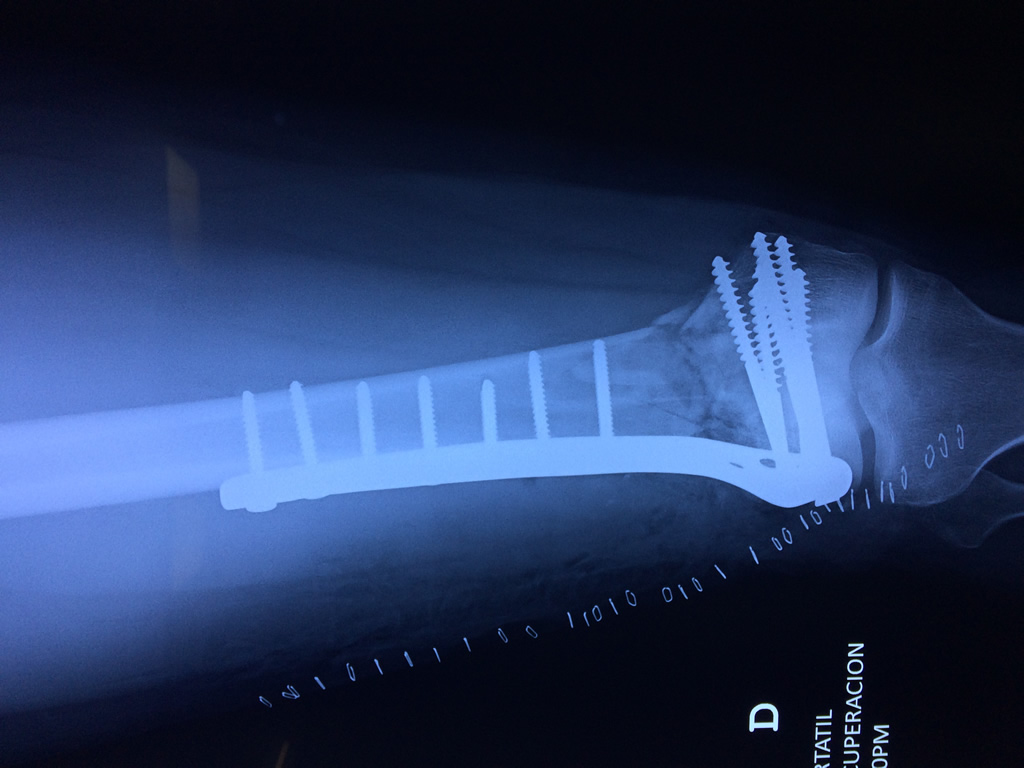

Cirugías de Cadera

El fémur es el hueso del muslo, el segundo segmento del miembro inferior. Es el hueso más largo, fuerte y voluminoso del cuerpo humano.